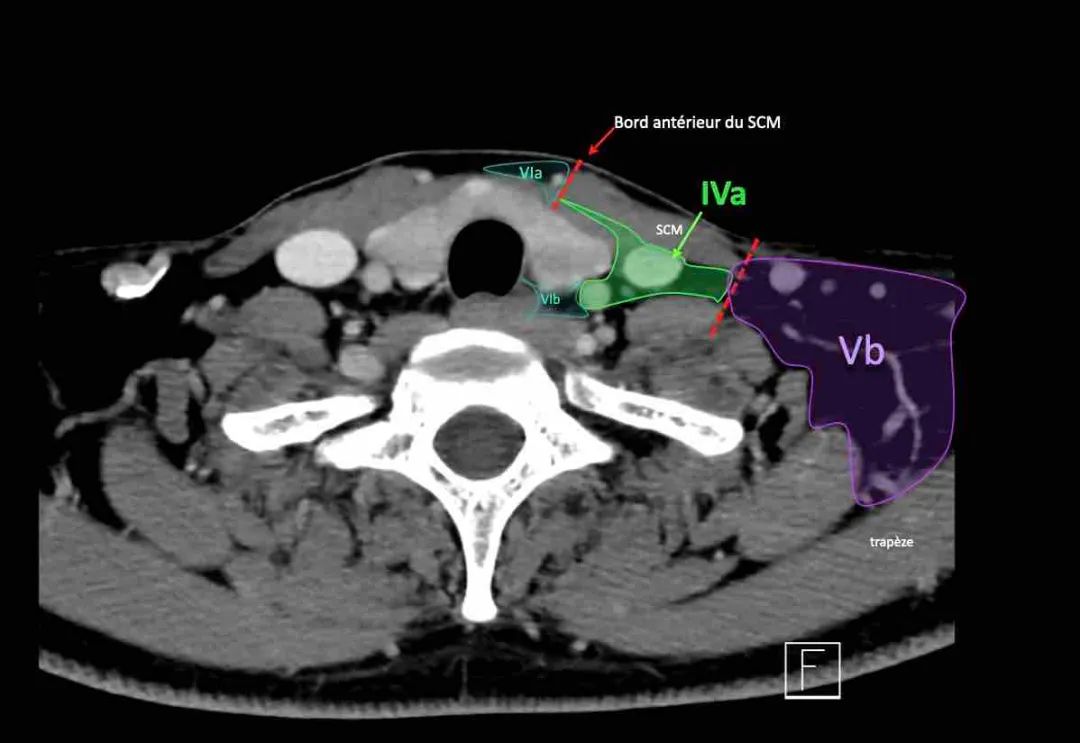

IV -下颈静脉和锁骨上内侧IVa和IVb水平之间的边界设置在距胸锁关节2 cm的颅侧。

IVa级

这些淋巴结有隐藏来自下咽癌、喉癌、甲状腺癌和颈段食道癌的转移的风险。

IVb级这些淋巴结有隐藏来自下咽部、声门下喉、气管、甲状腺和颈段食管的癌症转移的风险。